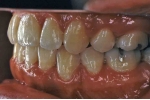

(左:治療前、右:治療後)

第4症例 Class Ⅱ divison 2 (overbite 5mm以上)

しかし、出題基準にも書いてあるように、このケースは欧米の白人によく見られるケースで、東洋人にはきわめて稀である。そこで類似ケースとして過蓋咬合(かがいこうごう)のケースを代替えとして認めるという配慮をしている。過蓋咬合とは非常に強く深く咬んでいる状態を言う。Overbiteとは前歯の垂直的な重なり具合を示す数値で、5mm以上だと上の前歯が下の前歯をほとんど覆い尽くしている感じになるので、前から見ると下の前歯はほとんど見えない状態になる。こういう状態が典型的な過蓋咬合である。典型的なclassⅡ,division 2のケースは過蓋咬合を合併している。